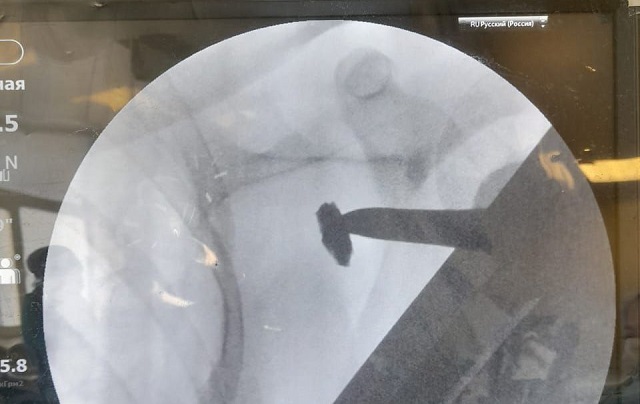

В  медучреждении отметили, что подобное хирургическое вмешательство требовало хорошей визуализации, потому его проводили под рентген-аппаратом.

На  протяжении всей операции на  экране можно было наблюдать, как хирург работает инструментом и  скрупулезно ищет осколок. Пациент в  это время находился под общим наркозом. В  настоящее время боец находится под наблюдением врачей и  готовится к  выписке.